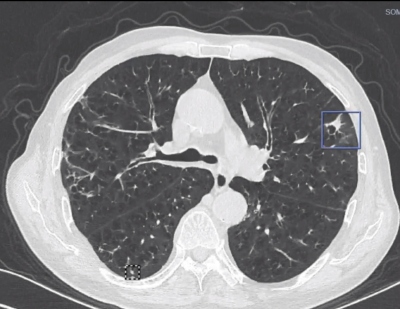

肺結(jié)節(jié)、肺部腫瘤、肺癌、肺部囊腫都是一個(gè)意思嗎?

哪些肺部結(jié)節(jié)可能屬于高危結(jié)節(jié)?

生活習(xí)慣對(duì)肺部結(jié)節(jié)的影響

肺部結(jié)節(jié)的類(lèi)型有哪些?